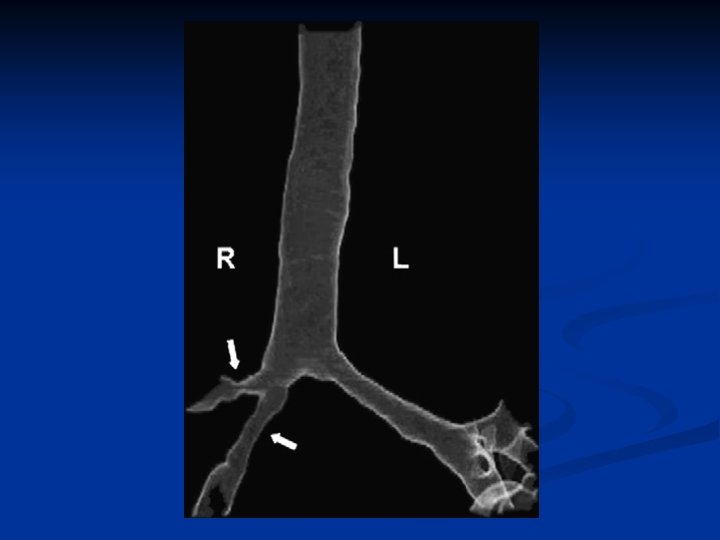

15 -55% DOS PTES COM GW OCASIONALMENTE É A ÚNICA APRESENTAÇÃO ANCA NEGATIVO EM 20% DESSES CASOS ROUQUIDÃO TOSSE DISPNÉIA HEMOPTISE CORNAGEM SIBILOS POLYCHRONOPOULOS VS ET AL. AIRWAY INVOLVEMENT IN WEGENER’S GRANULOMATOSIS. RHEUM DIS CLIN N AM 2007; 33 755– 75

VASCULITES PULMONARES PRIMÁRIAS SINAIS SENTINELAS HEMORRAGIA ALVEOLAR DIFUSA GLONERULONEFRITE AGUDA LESÕES ULCERATIVAS DE V. A. S. RX DE TÓRAX COM LESÕES NODULARES E/OU CAVITÁRIAS LESÕES DE PELE: PÚRPURA, BOLHAS, ÚLCERAS MONONEURITE MULTIPLEX DOENÇAS SISTÊMICA